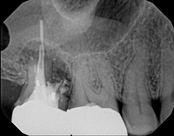

Non-surgical root canal treatment:

Before

Immediately After

6-month follow-upThis patient presented with pain when chewing. Diagnostic testing was done and determined it was the lower molar. The diagnosis was: pulpal necrosis, symptomatic periradicular periodontitis. Root canal treatment was performed with laser disinfection. The tooth had a crown and we accessed the tooth through the crown. We saved the tooth and the crown.